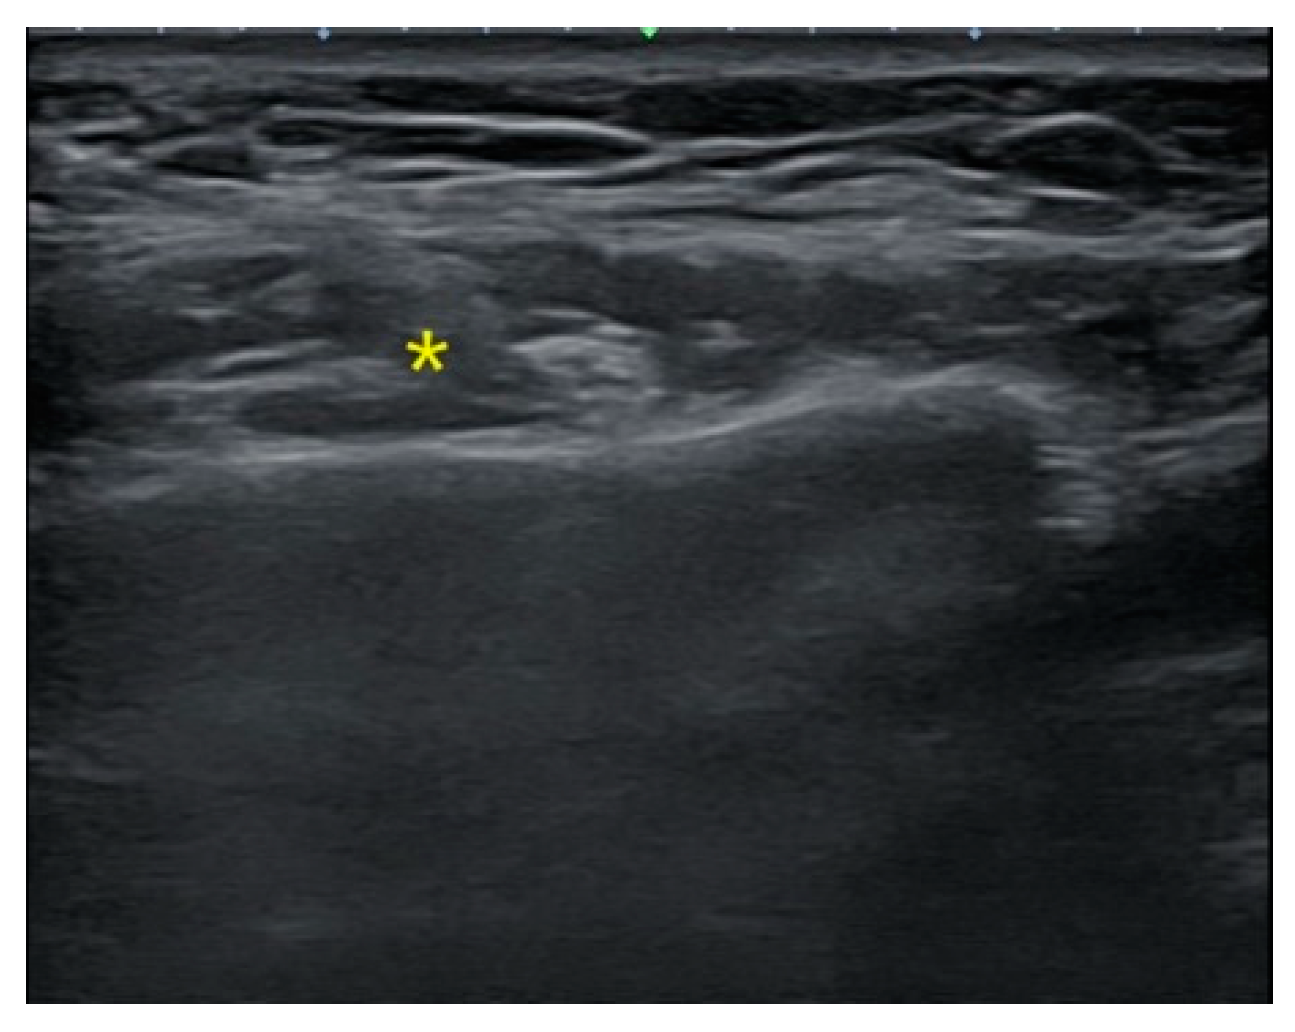

Figure 2. Ultrasound image before BoNT-A injection. Prior to the procedure, the thickest location of the masseter muscle was pre-identified using ultrasound. (* represents the thickest part of the masseter muscle).

The patient, who had previously received Botox injections in one masseter muscle using the landmark-guided, three-point injection technique, underwent injections on the opposite side of the face using the US-guided, single-point injection approach. Following the previously described method for masseter muscle assessment, the thickest region was identified using US B-mode, and its thickness (mm) was measured (Figure 2). Subsequently, with the US probe fixed in place, the injection needle was carefully guided into the muscle, ensuring proper and effective administration of the injection (Figure 3). Once it was confirmed that the injection was appropriately delivered at the thickest part of the muscle, the needle angle was adjusted to approximately 30 degrees in a thread-like manner to ensure even distribution of the drug throughout the remaining muscle parts (Figure 4). The needle was then withdrawn. The injection dosage remained consistent with the side that underwent landmark-guided, three-point injection.